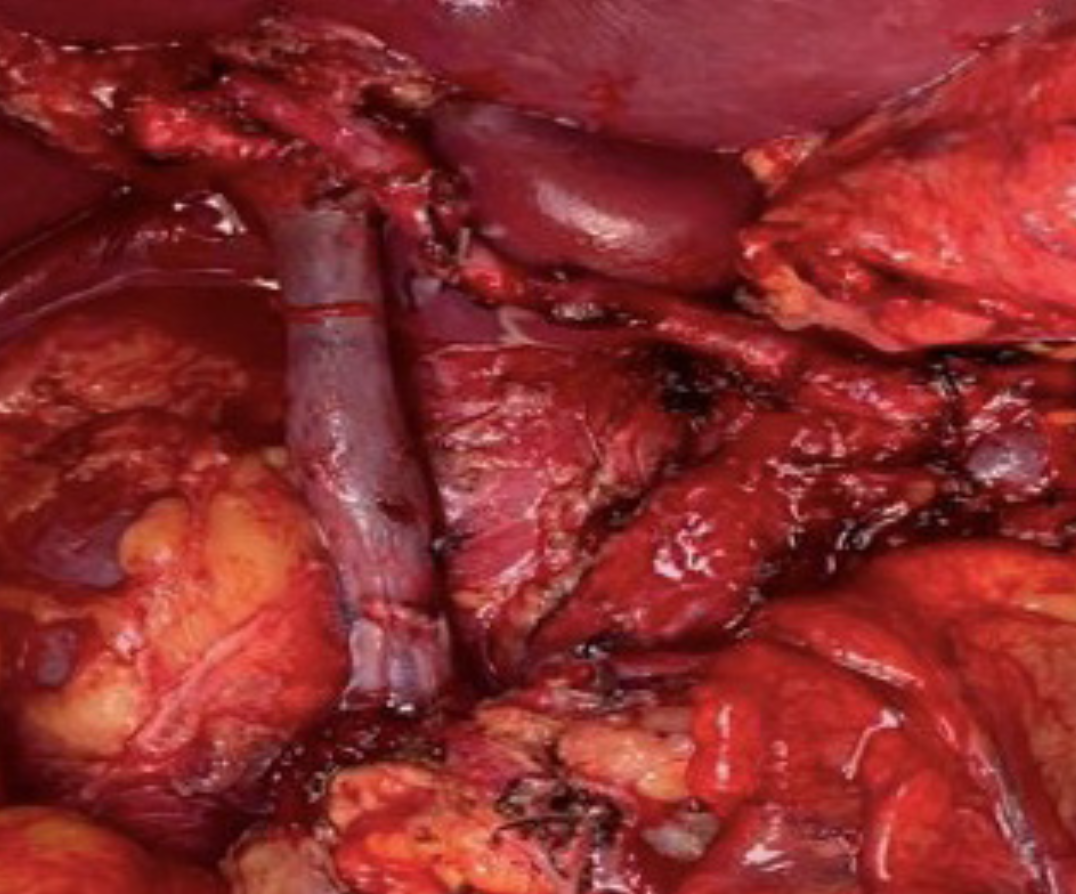

Imágenes y Cirugía

|

Diego Soto V, Cristian Marín O, Sebastián Morales Z